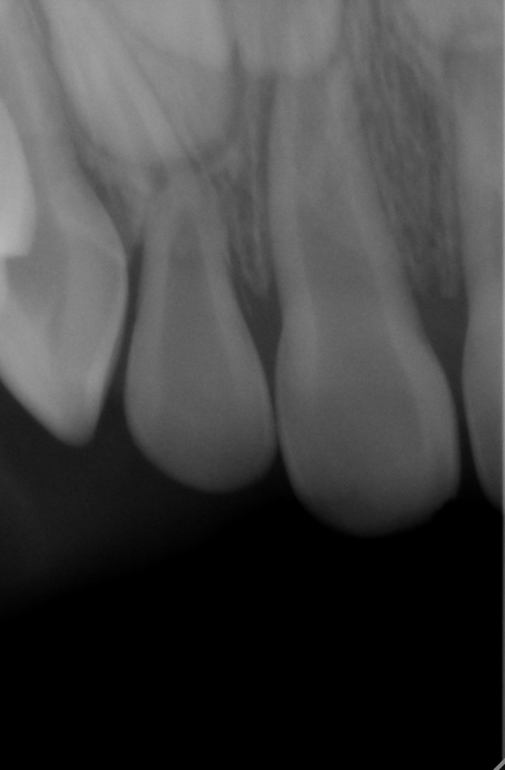

Здравствуйте!Подскажите пожалуйста что делать?Ребенок упал 6 марта этого года и дарился о железную ограду,было много крови и подвижность зубов.Также верхняя губа вздулась и и стала в 3 раза больше чем нижняя, сильная гематома.При походе к нашему врачу сказали,что пока мазать гепариновой мазью,но через два дня верхнюю губу пришлось вскрыть и наложить дренаж,т.к.было сильное уплотнение.По истечении 1,5 недель я увидела что два передних центральных зуба приобрели более серый оттенок по сравнению с другими, преимущественно в верхней части,где десна.Врач сказал что нужно удалять пульпу с нервами и что зуб уже не восстановится.Примечательно еще то что у нас ровно год назад тоже была травма,также припухла губа,но не было гематомы и зуб пострадал верхний левый центральный, который через две недели посерел и тоже говорили,что он таким и останется по цвету, но через полтора месяца он восстановился и по цвету не отличается от других зубов.Вчера 27 марта мы были у другого стоматолога и без снимком, а просто осмотрев зубы (т.к. снимки у нас в электронном виде на почте) он сказал, что правый центральный верхний зуб нужно полностью удалять,т.к. он уже и мертвый,между губой и десной образовался свищ и удалять просто нерв, а сам зуб оставить черевато может быть тем,что инфекция может остаться в корне зуба и и повлиять на коренной зуб.А если удалить полностью, то мы исключим это.Могу прикрепить снимки,которые были сделаны в тот же день,6 марта,после удара.Что вы можете сказать,очень важно ваше мнение тоже?Заранее огромное спасибо!